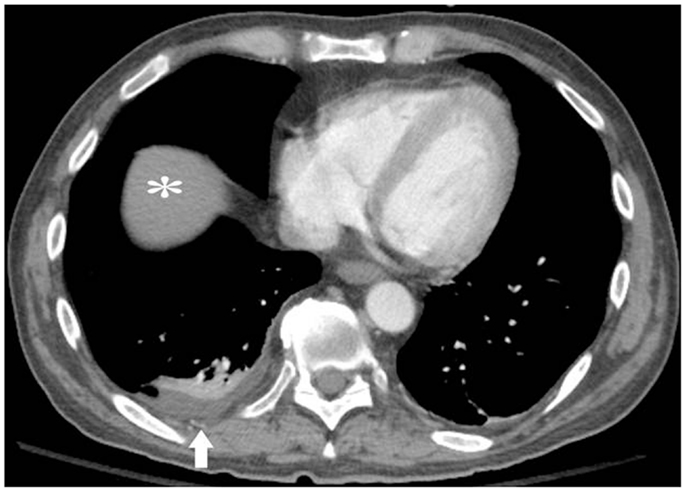

The patient had pericardial and exudative pleural effusions (Figure 1) causing increased oxygen requirement. He underwent thoracentesis and pericardiocentesis. Work-up for infectious, rheumatologic, and cardiac causes of the effusions was negative. Cytology of both effusions revealed reactive mesothelial cells in a background of acute inflammation, but no malignant cells were identified. Flow cytometry was done, and the cells in both the pleural and pericardial fluid were predominantly (70%) of a phenotype consistent with basophils. Repeat thoracentesis with cytogenetic analysis was performed. Fluorescent in situ hybridization was significant for trisomy 8, trisomy 9, and trisomy 21 in the pleural effusion. These cytogenetic abnormalities were identical to the those detected on the presenting bone marrow, and were found in the majority of the cells analyzed, thereby confirming the presence of leukemic pleural effusions.

Figure 1. Pre-treatment computed tomography (CT) image with intravenous (IV) contrast, demonstrating bilateral pleural effusions (white arrows) and moderate-sized pericardial effusion (black arrows), prior to thoracentesis, pericardiocentesis, or chemotherapy. Black asterisk = atelectatic lung.